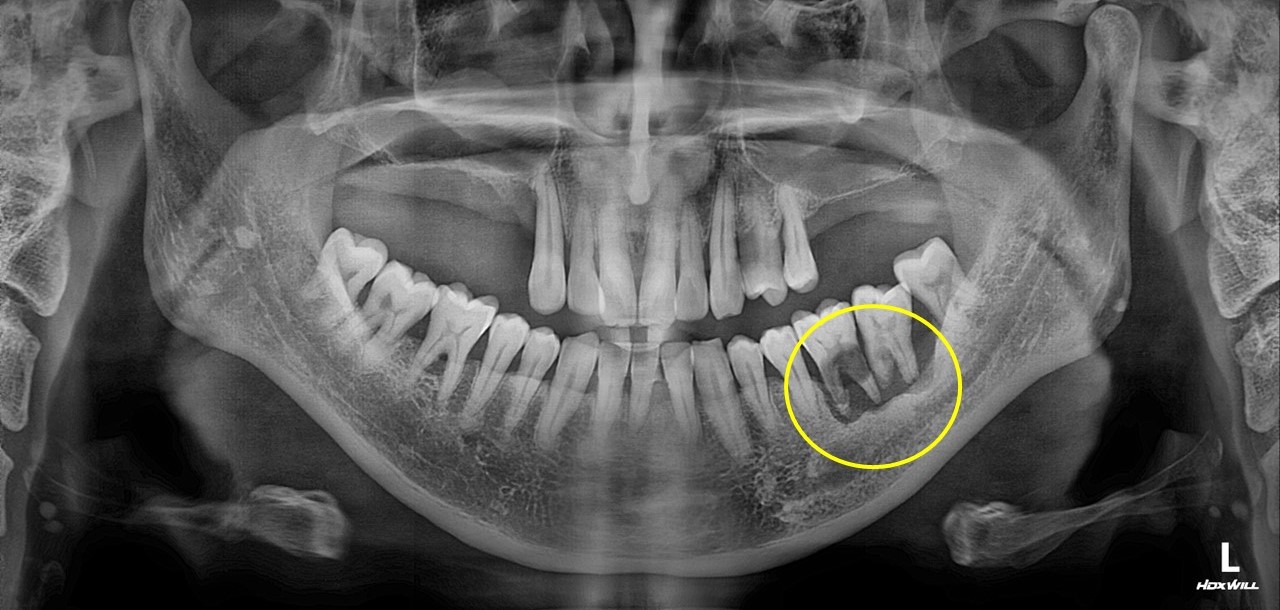

치조골 이식술 사례